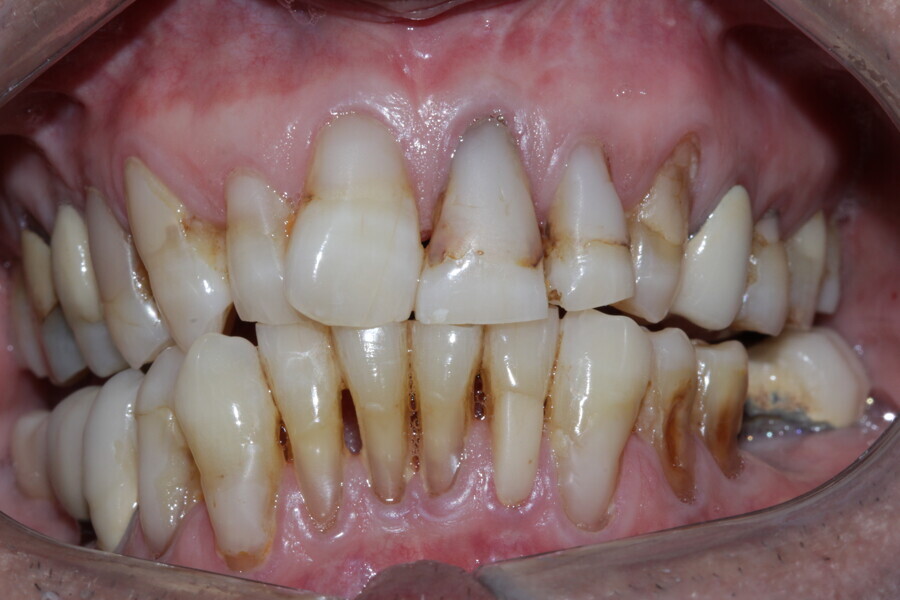

Figure 3 Anterior guidance before treatment